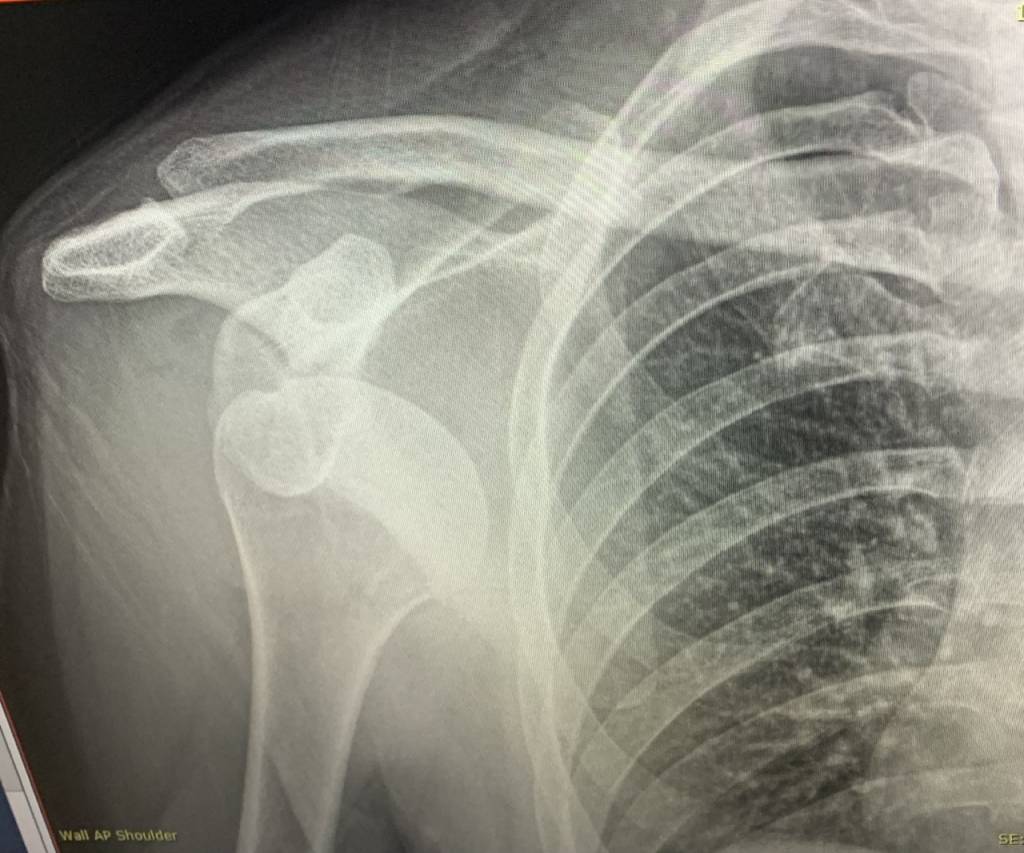

Ffs. Went to Dyfi Bike Park since Hardline wasn’t on today. Had a great time, rode a new to me line, Muddy Berms or something. Great fun. Until a sort of double drop thing with some very slippery woodwork in there, so I thought I’d be sensible and walk down it. Because I have things to do, like bikes to test, and Ard Rock to go to. Slipped, twisted my right arm out behind me, textbook dislocation. Long and uncomfortable walk down some gnarly drops with my arm dangling from my side, followed by a trip in an ambulance with my arm propped out like a wing. Couldn’t get it close in to my body for a sling etc, just excruciating. It’s back in now, sling for 2 weeks minimum. Gah.

I dislocated my right shoulder doing something equally (perhaps even more) benign 10 days before Christmas. It turned out I was super lucky - first time dislocation - I did chip my humeral head though.

Dyfi gave me that penthrox, I reckon it made one notch of difference on the pain scale. Husband maintains that morphine was very effective on me, I disagree. It just makes me chatty and I can’t feel my legs while still in loads of pain, maybe just two or three notches lower. Whatever they gave me for the relocation was good though, because I can’t remember that happening at all.